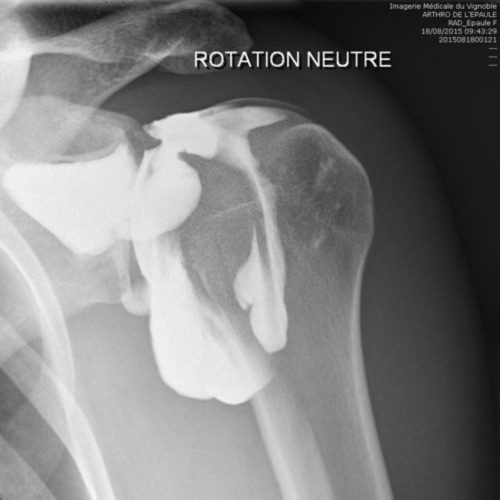

L’arthrographie

![]()

Cet examen consiste à injecter à l’aide d’une aiguille un liquide iodé à l’intérieur d’une articulation. Des clichés radiographiques permettent ensuite d’étudier le contenu de l’articulation.

L’examen est réalisé au cabinet de radiologie, en position allongée. La peau est d’abord désinfectée. La piqûre est un moment un peu désagréable de l’examen. L’injection du liquide iodé dans l’articulation ne provoque tout au plus que des douleurs modérées et très passagères. Après avoir retiré l’aiguille, votre articulation sera placée dans différentes positions et on prendra plusieurs clichés.

L’arthrographie sera le plus souvent complétée immédiatement par un scanner ou une irm de l’articulation. Ceci ne nécessitera pas de deuxième piqûre. Vous devrez donc vous rendre immédiatement après l’injection à l’hôpital pour la réalisation du scanner ou de l’irm.